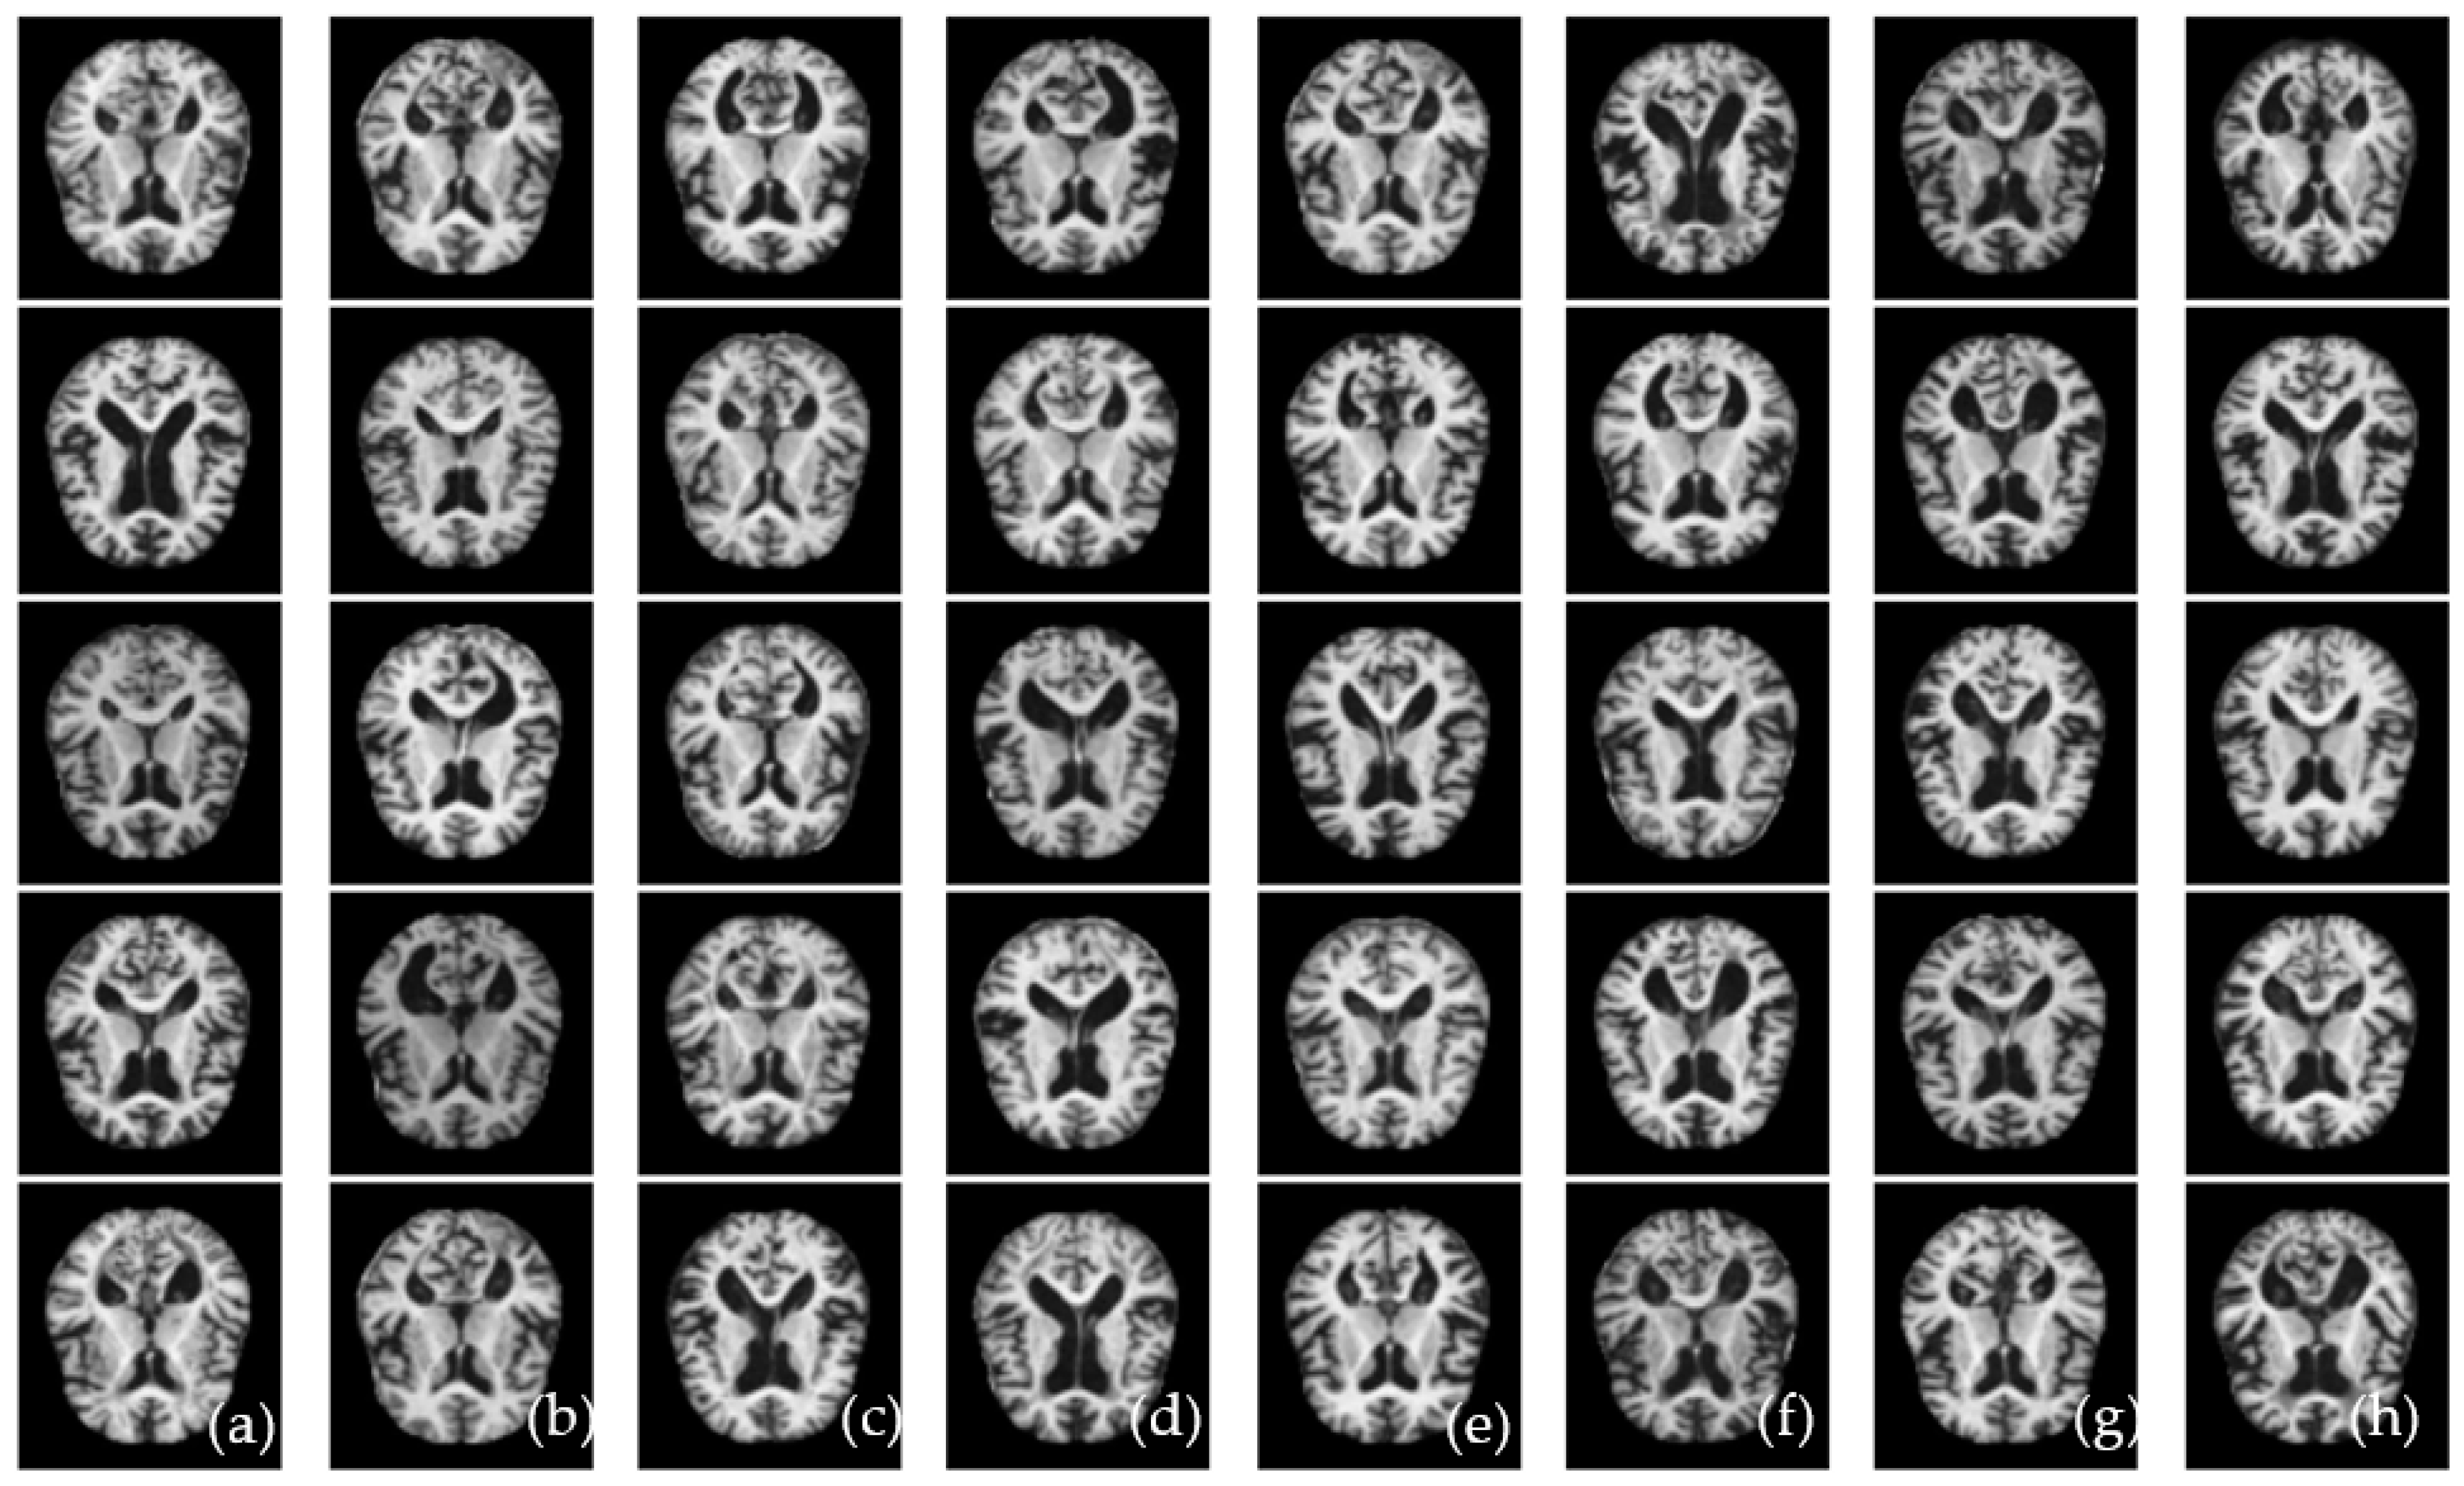

Figure 10.

A visual example of classification of CAD-ALZ system for recognition of AD disease on Kaggle-ALZ (a–h), where figure shows normal (a,e), mild dementia (b,f), moderate dementia (c,g), and very mild dementia (d,h).

On average, the proposed CAD-ALZ system as shown in Figure 9a outperformed (SE of 93%, SP of 96%, 94%, ACC of 0.95, PR of 0.98, Kappa of 0.99, F1-score 99%) on five classes of Kaggle-ALZ compared to A3C-TL-GTO-Xception (SE of 87%, SP of 88%, ACC of 89%, PR of 0.88, Kappa of 0.87, F1-score of 88%) and A3C-TL-GTO-MobileNet (SE of 87%, SP of 88%,ACC of 89%, PR of 0.88, Kappa of 0.87, F1-score of 88%). In the case of Figure 9b, the ADNI dataset is used to classify ALZ into three classes. On average, the proposed CAD-ALZ system outperformed (SE of 93%, SP of 96%, 94%, ACC of 0.95, PR of 0.98, Kappa of 0.99, F1-score 99%) on three classes of ADNI compared to A3C-TL-GTO-Xception (SE of 88%, SP of 89%, ACC of 90%, PR of 0.89, Kappa of 0.88, F1-score of 89%) and A3C-TL-GTO-MobileNet (SE of 89%, SP of 90%, ACC of 90%, PR of 0.89, Kappa of 0.89, F1-score of 90%). Those statistical results indicate that the proposed CAD-ALZ system is effective and provides a generalized solution for the classification of four stages of ALZ disease. A visual example of Figure 10 shows the result produced by our proposed CAD-ALZ system.